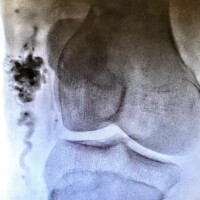

Congenital arteriovenous malformations can be present anywhere in the body but have a predilection for the brain, spinal cord, and the extremities. Rarely arteriovenous malformations of the internal organs such as the kidneys, the intestines, and the lungs can be detected. Early referral to a dedicated center of excellence is key. Diagnosis will inevitably depend on a series of imaging studies such as ultrasound, MRI, and angiography. Treatment is almost always indicated to minimize symptoms and decrease the likelihood of expansion and organ loss. In some rare cases, the malformation has expanded severely enough such that treatment may provide little to no benefit and management is geared more towards palliation of associated symptoms.

The mainstay of treatment for arteriovenous malformation is catheter-based embolization. The term embolization refers to delivery of certain particles or substances as closely as possible into the focus of the arteriovenous malformation. These particles or substances will then act to shut down the malformation by disrupting the blood supply to the focus of the malformation and redirecting blood flow back into the normal circulation. Most commonly, multiple treatment sessions will be required throughout the lifetime of the patient. It is important to emphasize that there is no cure for arteriovenous malformations and that treatment is aimed at minimizing symptoms and slowing the progression of the disease. Even with successful treatment, certain severe cases can continue to expand and cause organ and/or life-threatening problems.